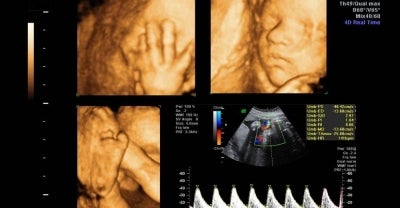

Mana tidaknya, meski mempunyai sistem pencernaan wanita, namun hasil imbasan USG mendapati Raras mempunyai alat kelamin lelaki tetapi kedudukannya lebih ke dalam.